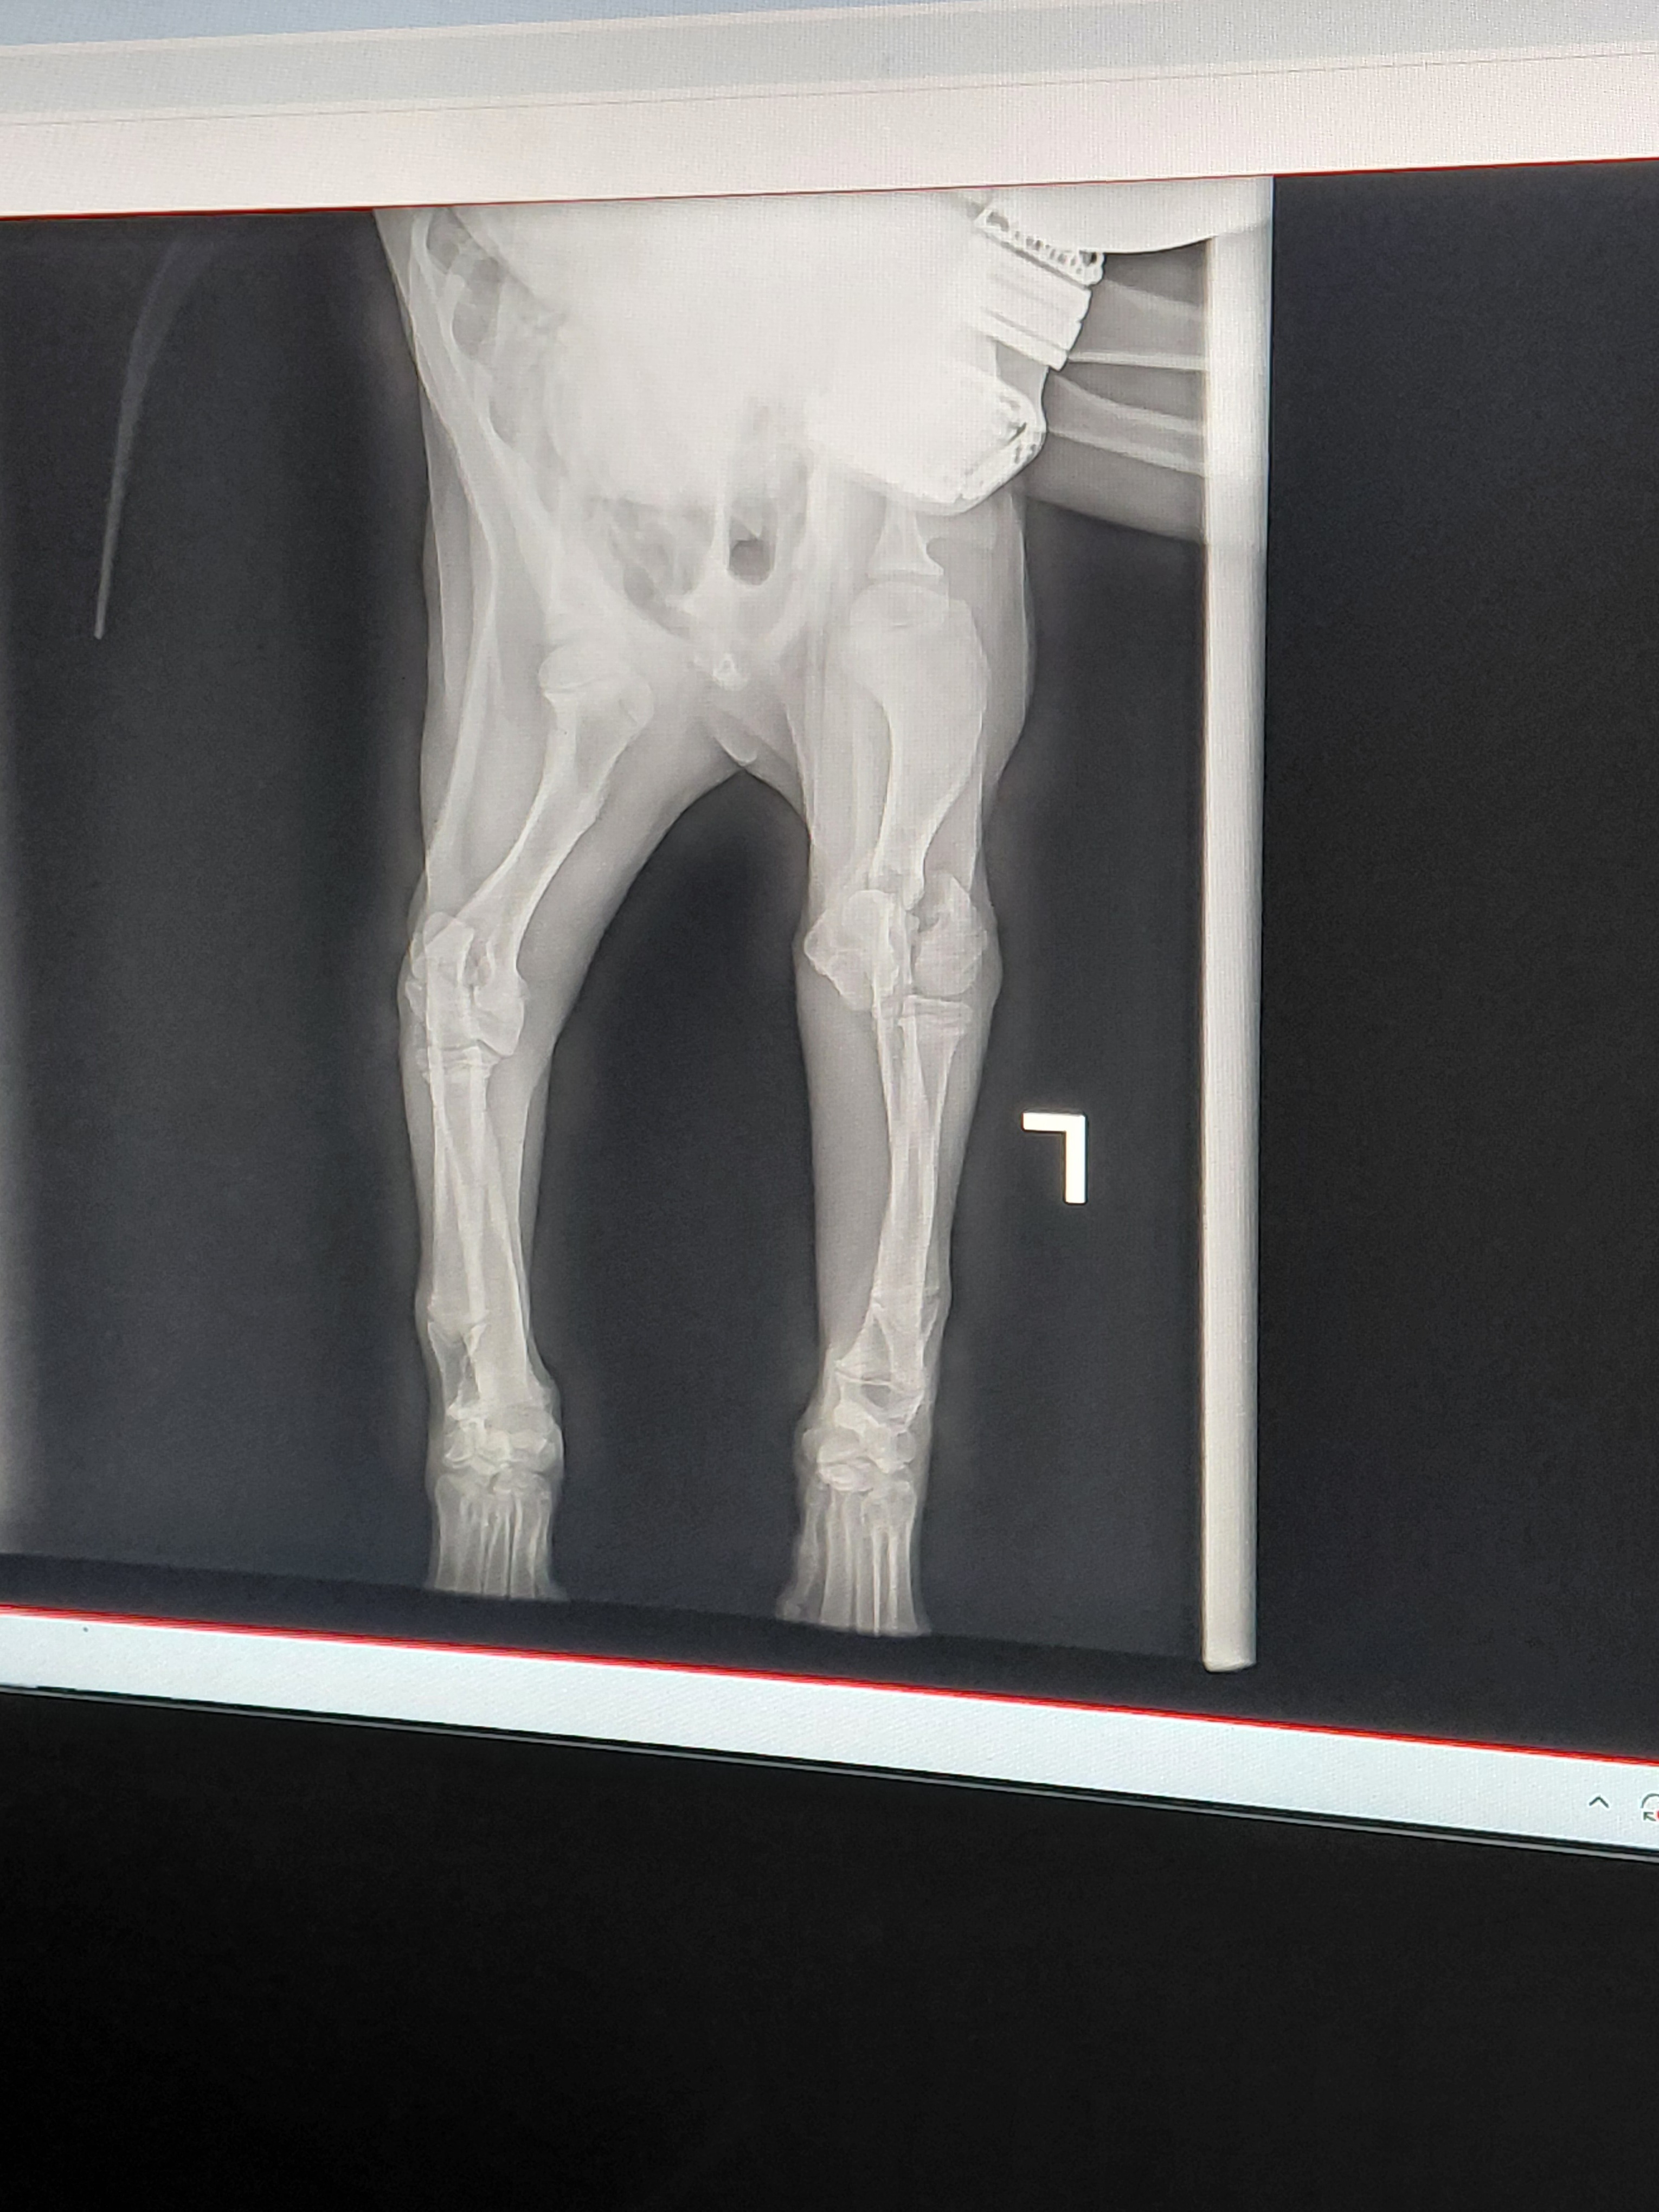

This fundraiser is for our 4 month old puppy Blue who injured his leg while playing outside.he fell and has a TY fracture.and it will need to be Amputated. . Amputation surgery and after care is more costly then we can afford. Any help would be very appreciated. Without the surgery the leg will not heal right and he will develop arthritis in the joint he will be in a lot of pain.